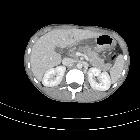

CT

- direct signs

- hypodense laceration or comminution of the pancreatic parenchyma

- heterogeneous parenchymal enhancement

- enlargement of the pancreas

- fluid collections (pseudocyst, abscess or hematoma) communicating with the pancreatic duct

- secondary signs

- peripancreatic fat stranding, fluid or hematoma between the pancreas and splenic vein

- peripancreatic fluid

- thickening of Gerota’s fascia

- injury to the pancreatic duct may not be seen directly but is inferred by the grading of the injury